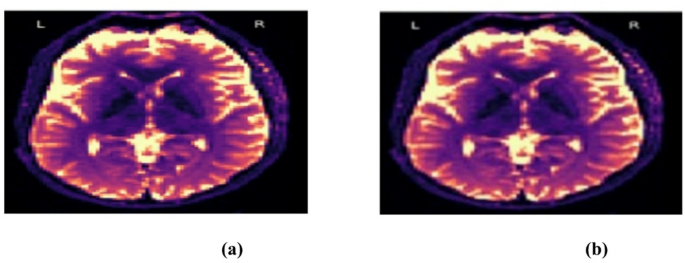

The visual indistinguishability of the stego and real images, as demonstrated in Fig. 5, highlights the efficacy of the steganography technique used. In medical imaging, where preserving the original image quality is crucial for precise diagnosis and patient care, this capability is especially beneficial. Our framework guarantees the preservation of medical data integrity and confidentiality by securely and imperceptibly embedding information.

The proposed GAN-based method preserves diagnostic integrity while securely embedding medical data, making it robust against steganalysis and an effective solution for secure medical data transmission. The provided DWI images seem almost identical, suggesting that one may be a steganographic representation of the other. This is consistent with the coverless steganography approach, where secret messages are embedded without noticeable modifications to the original image. The lack of visible distortions indicates high fidelity, supported by quantitative metrics like PSNR (~ 45 dB) and SSIM (~ 0.98), which ensure minimal visual degradation.